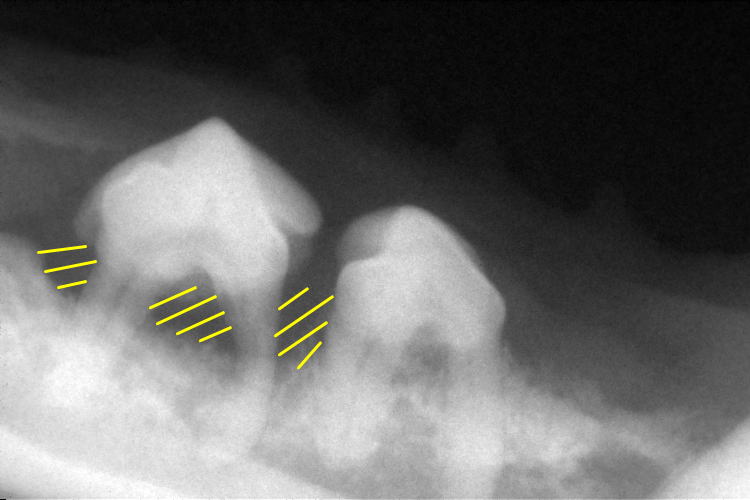

左下顎臼歯部分です。

第4前臼歯(左側)の歯根が変形しており、その周りの歯槽骨も溶けているのが分かります。